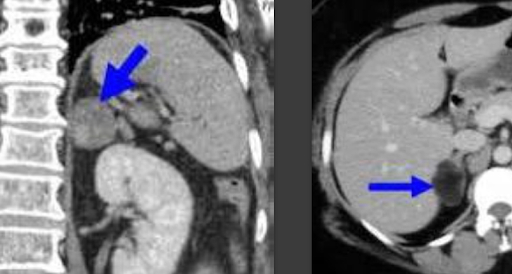

В НМИЦ онкологии имени Блохина мальчик поступил в крайне тяжелом состоянии с тромбозом нижней полой вены и синдромом Иценко–Кушинга. В результате обследования было обнаружено, что рак распространился на печень, забрюшинные лимфоузлы и лёгкие. Хирурги приступили к крайне сложной, но жизненно необходимой операции, в ходе проведения которой присутствовали практически все анестезиологи клиники.

Главная сложность заключалась в расположении опухоли - она тесно прилегала к печени, нижней полой вене, почке и диафрагме. Сначала нужно было ее выделить, а потом удалить тромботическую массу из нижней полой вены. Операция прошла успешно - опухоль с тромбом были удалены,а также восстановлена целостность вены. Дальше подростку предстоит реабилитация, но угрозы жизни нет, метастазы не выявлены.